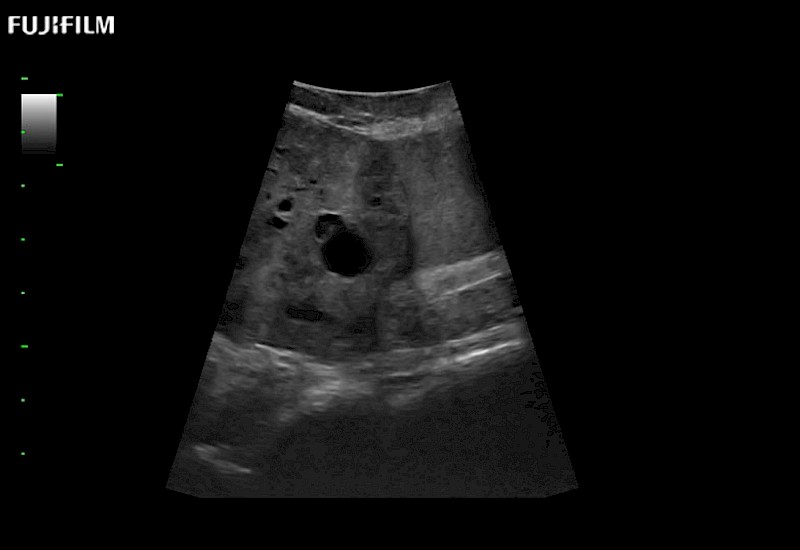

Our dedication to Laparoscopic Surgery allows us to offer superior image quality, outstanding system reliability and intuitive use of cutting edge technology.